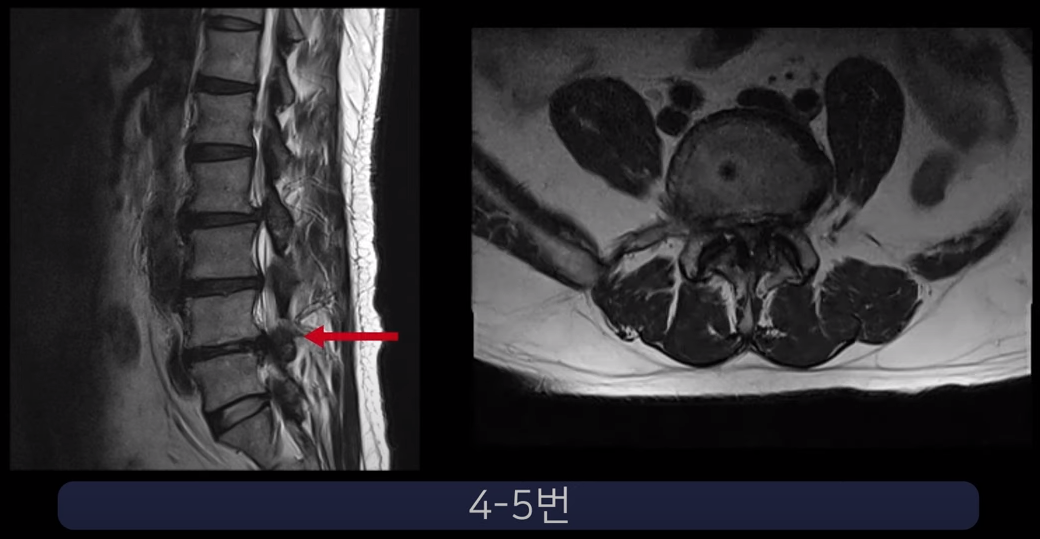

두 번째 환자분입니다. 이 환자분은 4-5번 오른쪽에 심한 추간공협착증, 그리고 2단계의 전방전위증이 있습니다.

그래서 이런 심한 협착으로 인해 다리에 마비까지 와서 걸음을 거의 걷지 못하셨습니다. 신경주사도 전혀 효과가 없어서 결국 수술을 결심해 대학병원과 9군데의 정형외과, 신경외과에서 수술상담을 했지만 어려운 수술이라고 하면서 척추유합술, 감압술 등 병원마다 제시하는 수술방법이 다 달라 많은 혼란을 겪으셨습니다.